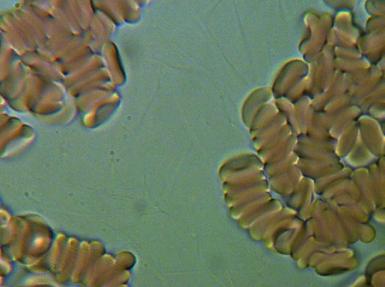

1.RULONIZACJA I AGREGACJA ERYTROCYTÓW

To poważne zagrożenie zatorowo - zakrzepowe, co klinicznie może spowodować zapalenie naczyń obwodowych, zawał serca, udar mózgu a nawet nagły zgon. Agregacji i rulonizacji nie można stwierdzić tradycyjnymi badaniami diagnostycznymi.